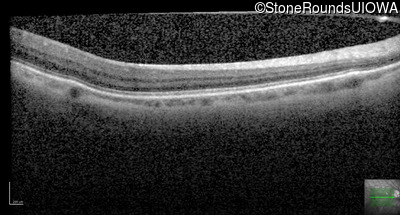

Age at visit: 32 years